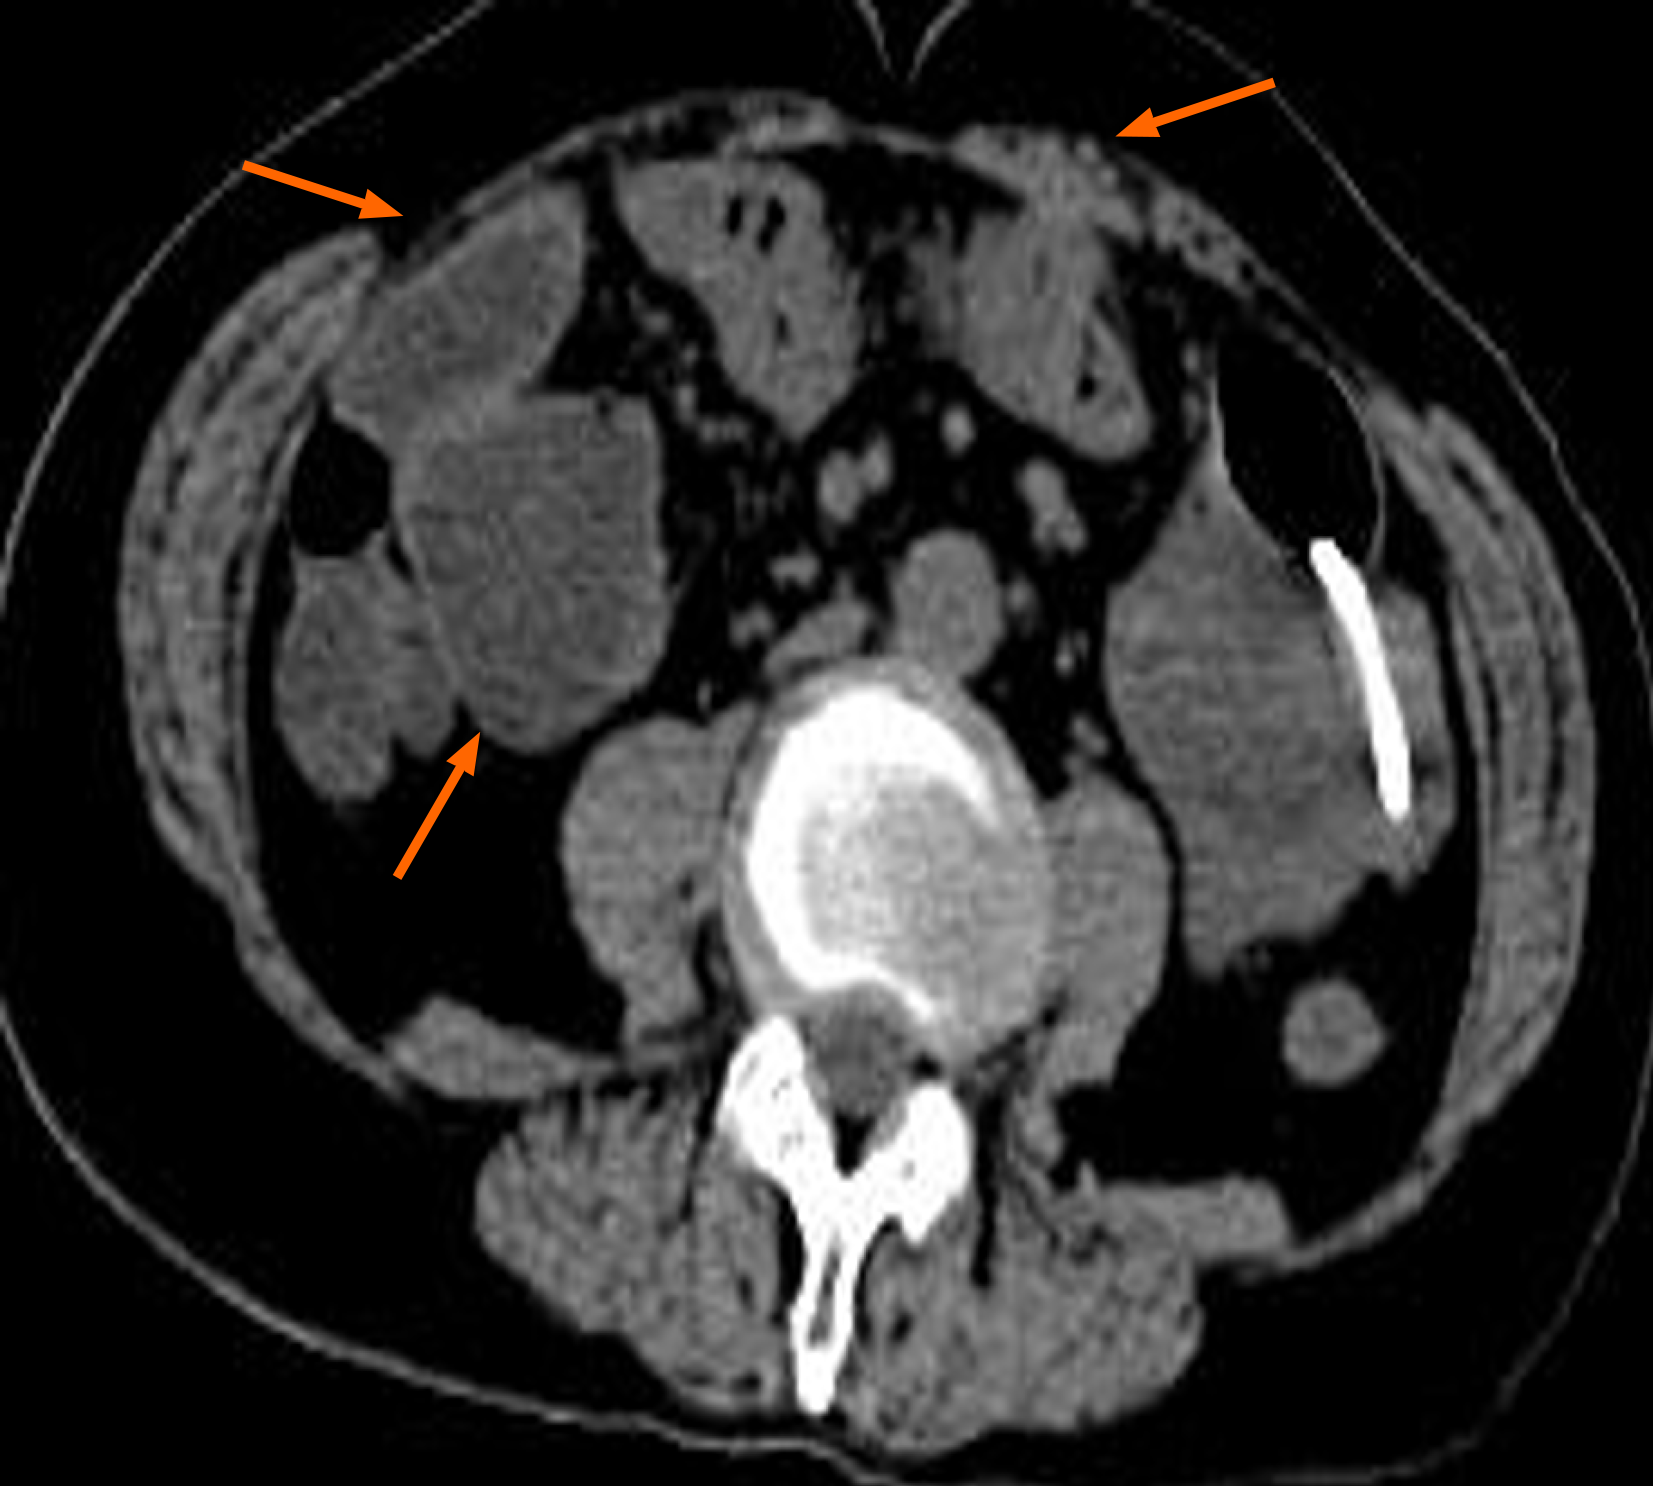

Figure 2

Figure 2 Representative whole-abdominal computed tomography images. Dilated intestinal collaterals are seen and adhesions of the small intestine to the abdominal wall are seen.

Abdominal upright plain film suggest gas accumulation in the abdominal intestine. Additionally, scattered fluid levels were observed, which illustrates intestinal obstruction (Figure 1). The CT of the chest and abdomen revealed the following findings: Lesions occupied the lower lobe of the left lung, accompanied by pleural hypertrophy in the adjacent pleura; Part of the intestinal tract was dilated, and air-fluid level could be observed in the intestinal ducts, which was considered intestinal obstruction (Figure 2); Multiple slightly enlarged lymph nodes were observed in the right middle and lower abdomen. Worse still, a diverse array of enlarged lymph nodes were observed in the groin bilaterally; An uneven elevation in bone density within the right ilium was suspected to be indicative of bone metastasis.